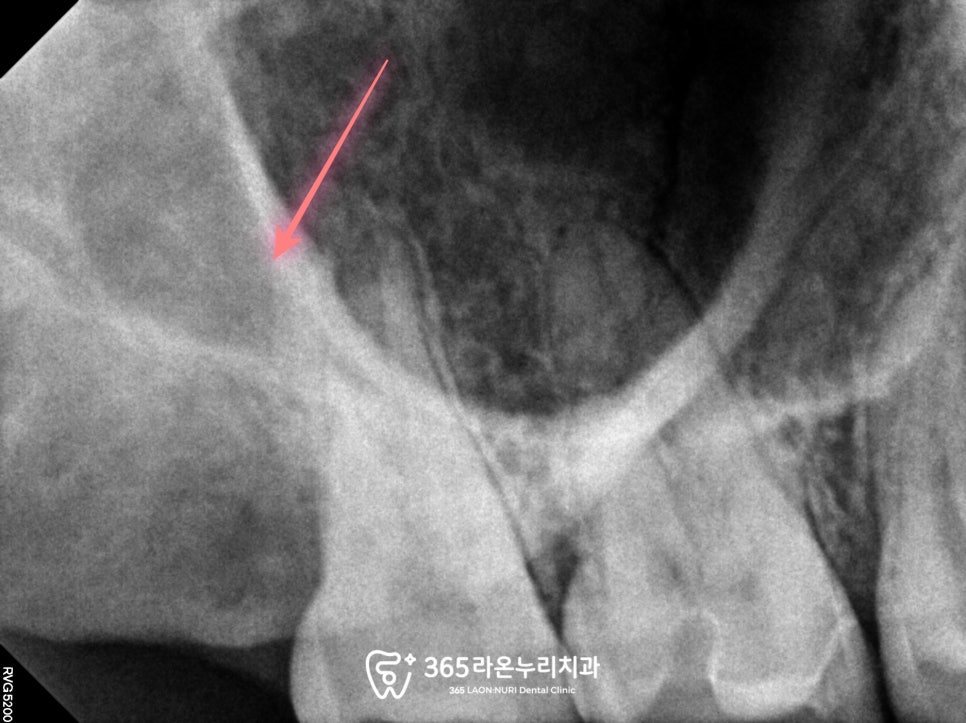

사랑니(18번)이

덜 맹출된 상태로 보였는데요.

그 옆을 자세히 살펴보면

아주 조그마한 과잉치도

볼 수 있습니다.

잇몸 밖으로 나오지 않은

사랑니는 추후 문제를

일으킬 수 있는 가능성이

아주 다분하기 때문에

발치를 결정하게 됩니다.